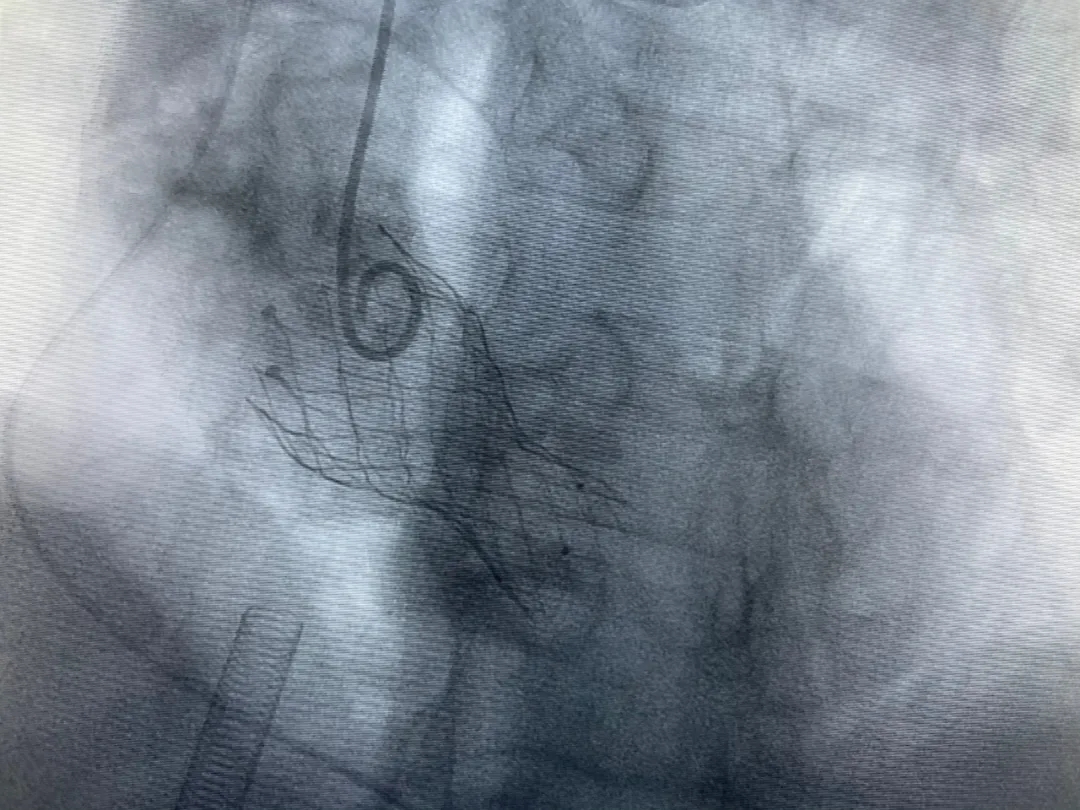

結(jié)合老人病情特點:年齡高、室壁厚、左室腔小、瓣膜鈣化嚴重,術(shù)中球囊擴張和瓣膜釋放過程有循環(huán)崩潰可能;為降低此種風險、最大程度提高手術(shù)成功率,張金洲副院長在術(shù)前組織了由楊金保博士帶領的TAVR團隊多次反復溝通、討論,制定了各種應急處理方案。最終經(jīng)過TAVR團隊的默契配合,手術(shù)歷時2小時,用20#球囊預擴張后順利植入23#主動脈瓣生物瓣膜,再次后擴后主動脈根部造影顯示:人工主動脈瓣生物瓣位置良好,瓣葉開閉正常;冠脈顯影良好。經(jīng)食道超聲顯示:主動脈瓣葉活動度良好,主動脈跨瓣壓差約35mmHg,未見瓣周漏及明顯返流。出手術(shù)室前老人便已蘇醒,自訴憋悶癥狀完全消失。